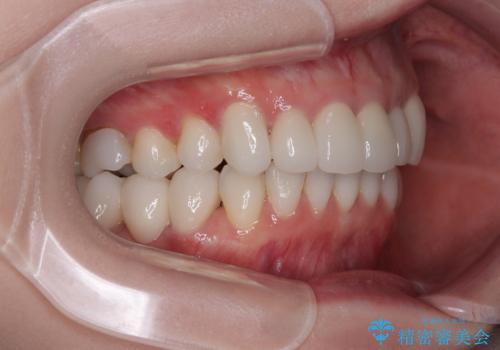

- 全体的なデコボコと、奥歯の欠損を放置した結果倒れ込んだ奥歯などを気にして来院された患者様です。

ワイヤー矯正の方が理想的な仕上がりとできる状態でしたが、上顎前歯にクラウンが装着されているため、インビザラインにて矯正治療を行うこととしました。

インビザラインのみで対応できないときにはワイヤー矯正を併用することとし、矯正治療後にはオールセラミッククラウンによる補綴治療を行うこととしました。

矯正治療自体はインビザラインで満足のいく仕上がりとなりました。

前歯は根管治療が必要となり、元々舌側に入り込んでいた左上2番目の歯は歯周外科処置により歯肉ラインを整えることとしました。

欠損部位は傾斜歯軸を起き上がらせることができたため、オールセラミッククブリッジにて補綴治療を行いました。

全顎的に満足のいく仕上がりとなりました。